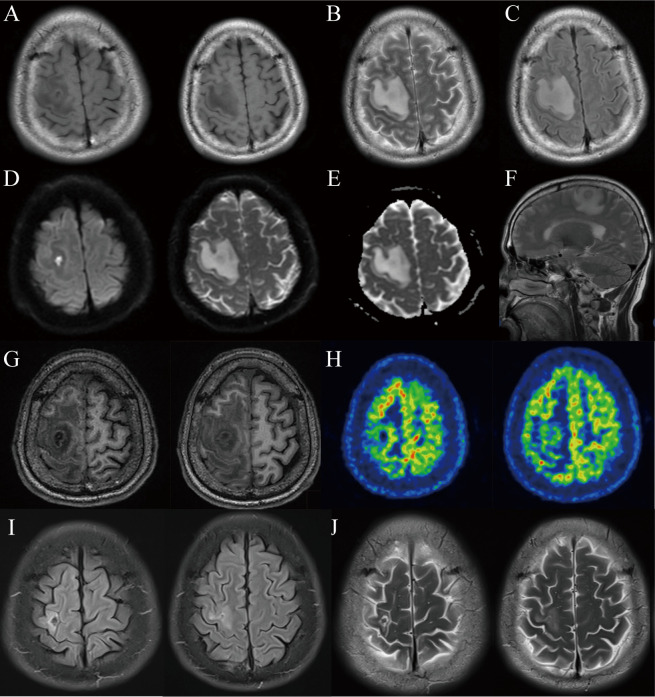

脑脓肿危及生命,死亡率高。尽管在敏感的成像技术、有效的抗菌疗法和复杂的外科手术方面取得了进步,但诊断和治疗脑脓肿仍然具有挑战性。虽然经验性抗菌疗法和神经外科手术被认为是脑脓肿的主要治疗方法,但其疗效受到潜在副作用的限制,包括中性粒细胞减少症的发生、重复手术的需要以及新发癫痫的风险。在此,我们介绍了一例 52 岁男性患者的病例,他出现阵发性抽搐并伴有左侧肢体无力和麻木超过 2 个月。尽管脑部核磁共振成像显示其右侧额叶有一个大小约为 28 毫米 × 19 毫米 × 21 毫米的多形性囊性病变,但患者拒绝接受神经外科干预。在完成为期 6 周的抗菌治疗后,患者寻求中医治疗。结果,经过 4 个月的中医治疗后,患者在约 60 天内没有再出现阵发性抽搐。8 个月后的核磁共振成像显示,右额叶的病灶缩小至 8 毫米×4 毫米。据我们所知,这是第一例有据可查的脑脓肿患者通过抗菌治疗和中医治疗相结合而获得成功的病例。该病例报告表明,中医药可为治疗脑脓肿等感染提供显著的辅助疗效。然而,要证实中草药治疗脑脓肿的疗效,还需要前瞻性研究的进一步证明。

Brain abscess is life-threatening and carries a high risk of mortality. Despite advances in sensitive imaging techniques, effective antimicrobial therapies, and sophisticated surgical procedures, diagnosing and treating brain abscesses remains challenging. Although empirical antimicrobial therapy and neurosurgery are considered primary treatments for brain abscesses, their efficacy is limited by potential side effects including neutropenia development, the need for repeat surgeries, and the risk of new-onset epilepsy. Here, we present a case of a 52-year-old male patient who experienced paroxysmal convulsions accompanied by left-sided limb weakness and numbness for over 2 months. Despite a brain MRI revealing a multilocular cystic lesion in the right frontal lobe, with about 28 mm × 19 mm × 21 mm in size, the patient declined neurosurgical interventions. After completing a 6-week course of antimicrobial therapy, the patient sought traditional Chinese medicine (TCM) treatment. As a result, the patient remained free of paroxysmal convulsions for about 60 days after a 4-month TCM treatment. A follow-up MRI imaging at 8 months showed a reduction in the size of the lesion in the right frontal lobe to 8 mm × 4 mm. To the best of our knowledge, this is the first well-documented case of a brain abscess that was successfully managed with a combination of antimicrobial therapy and TCM. This case report suggests that TCM may provide significant supplementary benefits in managing infections like brain abscesses. However, further evidence from prospective studies is necessary to substantiate the efficacy of Chinese herbal medicine for the treatment of brain abscesses.